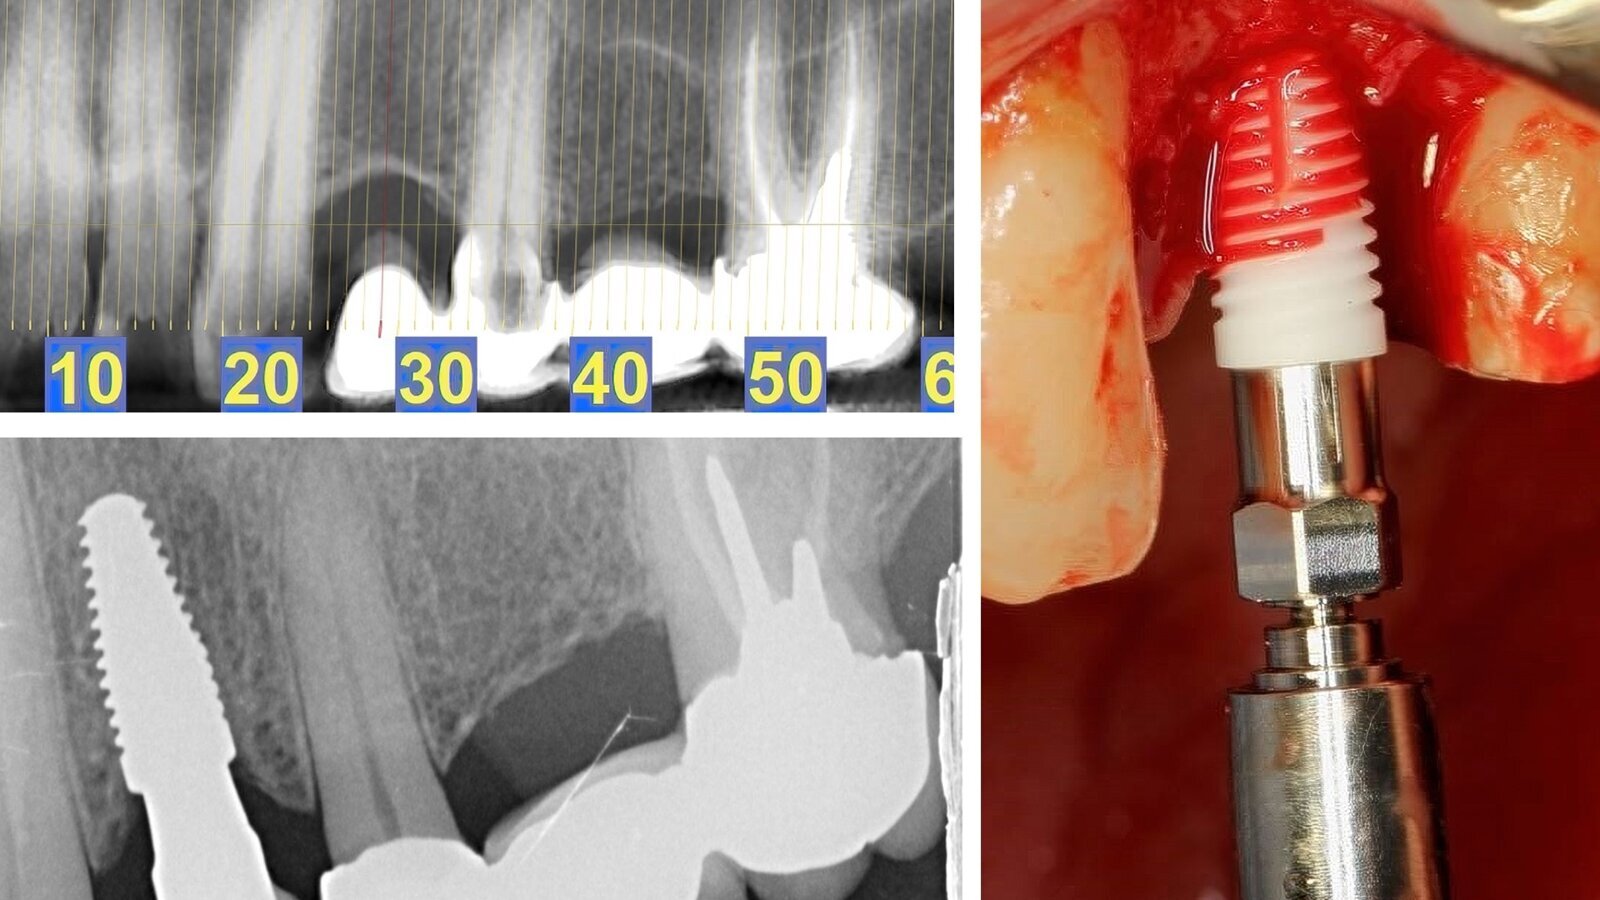

Situación inicial del caso clínico (arriba), colocación del implante Neodent Zi en la región 24 (derecha) e imagen radiográfica a los tres meses de la colocación de la corona (debajo a la izquierda).

Fig. 2. Colocación del implante cerámico Neodent Zi en la región 24.

Se colocó el implante Neodent Zi 4.3 × 10 con un torque final de 45 N.cm. Colocamos un tornillo de cubierta y, después de la sutura, colocamos el antiguo puente con cemento temporal.

Esperamos tres meses para la cirugía secundaria y colocar el muñón de cicatrización 4,5 × 2,5.

Quince días después de la segunda cirugía, realizamos un escaneo con un scan body del implante y del puente de 25 a 27. La corona final se colocó sobre el muñón Zi Base de 3,75 × 4 × 2,5. Se colocó la corona y el puente y se realizaron ajustes oclusales.

Fig. 3. Situación radiográfica después de la colocación del implante.

Fig. 4. Situación radiográfica después de la colocación de la corona final, seguimiento de tres meses.